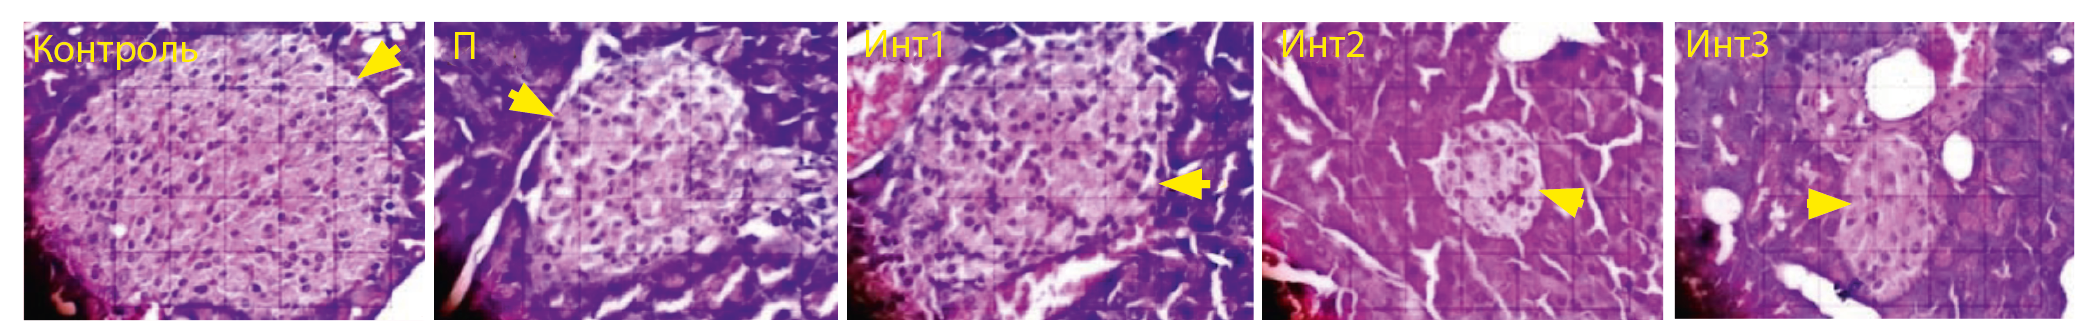

Островки поджелудочной железы

В контрольной группе наблюдались самые крупные островки поджелудочной железы, были обнаружены значительные различия с группами Инт2 и Инт3 (рис. 1 и 2).

Рис. 2. Площадь островков поджелудочной железы (стрелка) при окрашивании гематоксилином и эозином, микроскоп Nikon eclipse Ci, с увеличением 400x, Optilab Viewer 2.2, Image Raster 3.0.